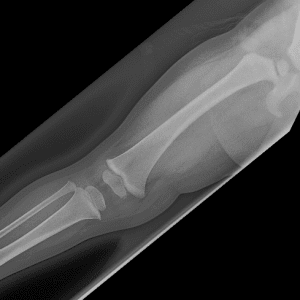

Pediatric Radiographs